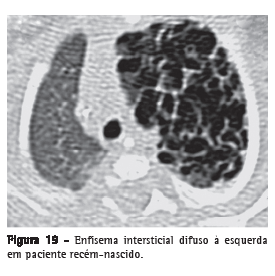

Enfisema intersticial

Dissecção do interstício pulmonar por ar, tipicamente localizado nos feixes broncovasculares, nos septos interlobulares e na pleura visceral, sendo mais frequentemente identificado em neonatos submetidos à ventilação mecânica (Figura 19). O enfisema intersticial dificilmente é reconhecido radiologicamente em adultos e é raramente identificado nos exames de TC. O processo expressa-se como áreas com densidade de ar com distribuição perivascular, peribroncovascular e/ou ao longo dos septos interlobulares (Figura 20), ou como áreas arredondadas de baixa atenuação simulando pequenas bolhas ou cistos (Figuras 19 e 20).(40,41)